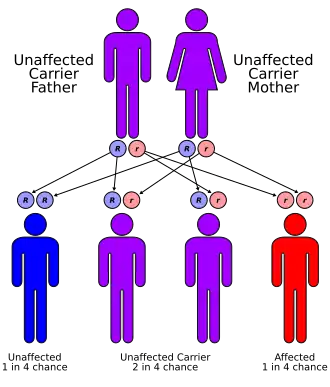

Situs inversus is generally an autosomal recessive genetic condition, although it can be X-linked or found in identical "mirror image" twins.[4]